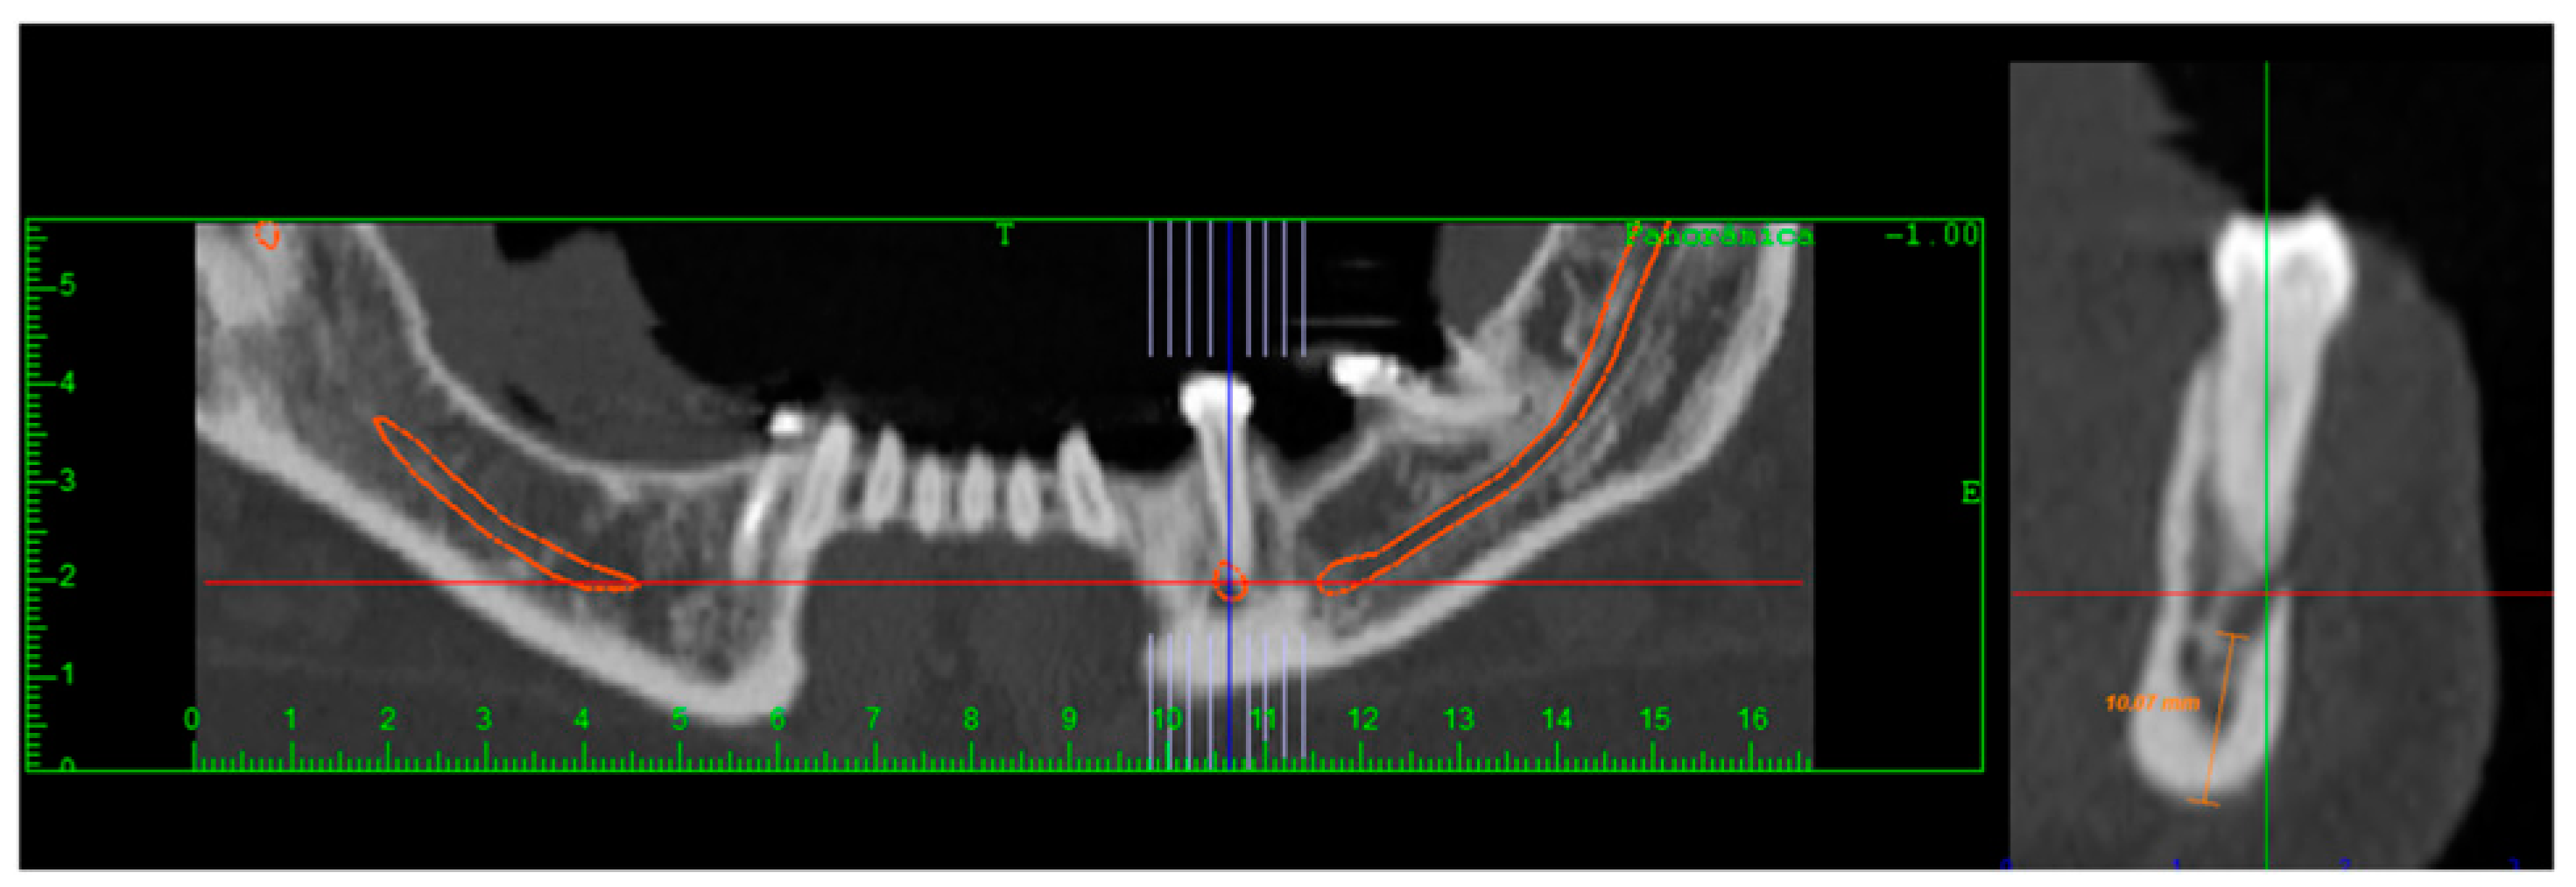

Tomographic Evaluation of Bone Height Between the Mandibular Canal and the Inferior Cortex of the Mandible Related to Bicortical Screws Fixation

Fares, R.D.; Leal, J.V.B.; da Silva Areas, M.Z.; da Rocha, H.V.; de Moraes, S.L.C.; Homsi, N.; da Silva, J.R. Tomographic Evaluation of Bone Height Between the Mandibular Canal and the Inferior Cortex of the Mandible Related to Bicortical Screws Fixation. Craniomaxillofac. Trauma Reconstr. 2024, 17, 181-185. https://doi.org/10.1177/19433875231213892